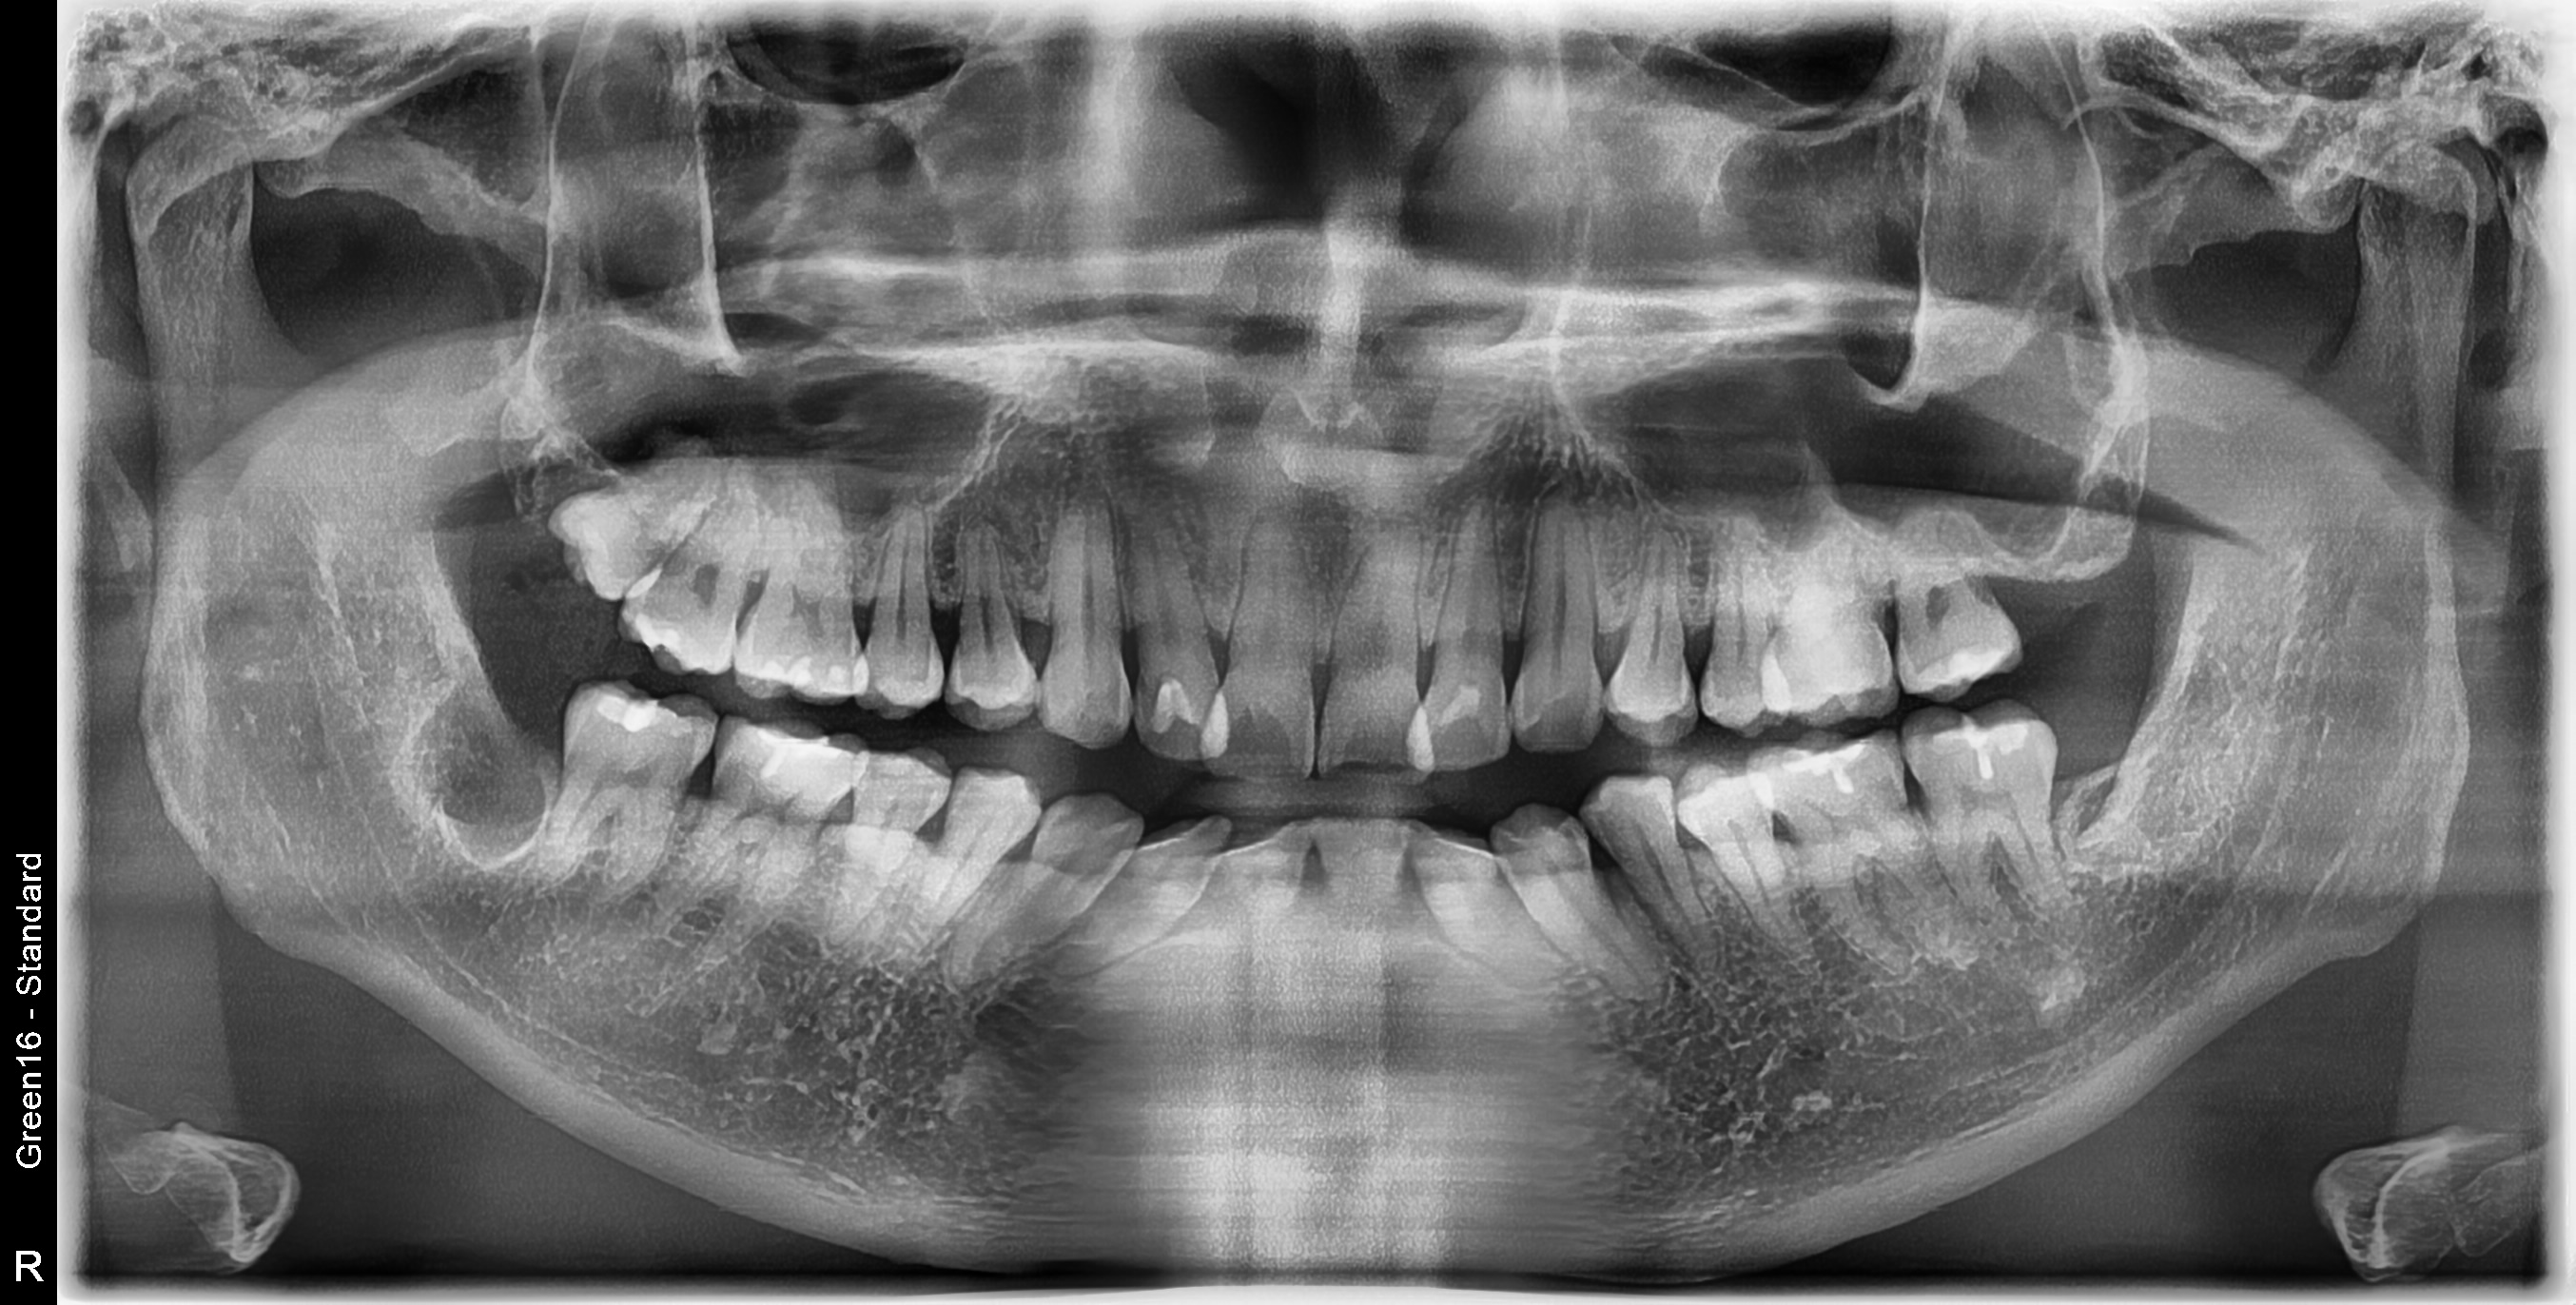

[악안면외과] 우측 매복사랑니 발치 난케이스 사례

방사선 검사를 통해 사랑니 위치와 신경과의 거리를 먼저 확인한 뒤, 가능한 경우에 한해 당일 발치를 도와 드려 갑작스러운 통증으로 인한 불편을 빠르게 줄이는 데 도움을 드립니다.

사랑니 뿌리근처에는 아래턱 신경이라는 커다란 신경이 지나갑니다. 개개인마다 다르지만 뽑는 과정에서 신경에 손상을 일으킬 가능성이 있습니다. 신경손상 가능성에 대한 사전 분석이 필요하며 손상가능성이 있다고 판단되는 경우 경험 많은 의사에게 조심스러운 발치 및 후처리가 요구됩니다.

매복사랑니는 매복된 위치에 따라 난이도가 다릅니다. 보통 잇몸 수술을 동반해서 치아 분할, 골 삭제가 이뤄지므로 많이 불편할 수 있는 과정입니다. 최소절개, 최소삭제를 원칙으로 발치를 진행하여 수술 기간과 후유증을 최소화합니다.